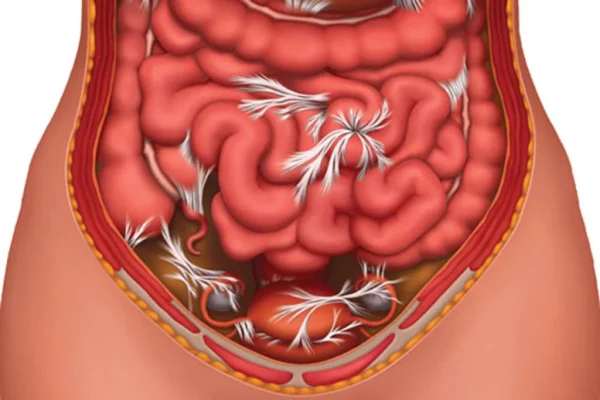

بیماری کرون:

التهاب مزمن و عمیق روده است که هر بخش دستگاه گوارش را درگیر میکند. علائم آن اسهال، درد شکم، کاهش وزن و خستگی است. درمان با داروهای ضد التهاب و در موارد شدید، جراحی است.

انسداد روده:

بسته شدن مسیر روده باعث یبوست، نفخ، دل درد و استفراغ میشود. علتش ممکن است چسبندگی، تومور یا پیچ خوردگی باشد. درمان فوری با دارو یا جراحی انجام میشود.

کولیت

التهاب مزمن روده بزرگ است که باعث زخم و خون ریزی میشود. نشانهها شامل اسهال خونی، دل درد و کاهش وزن است. درمان با دارو و در موارد شدید، جراحی کولون است.